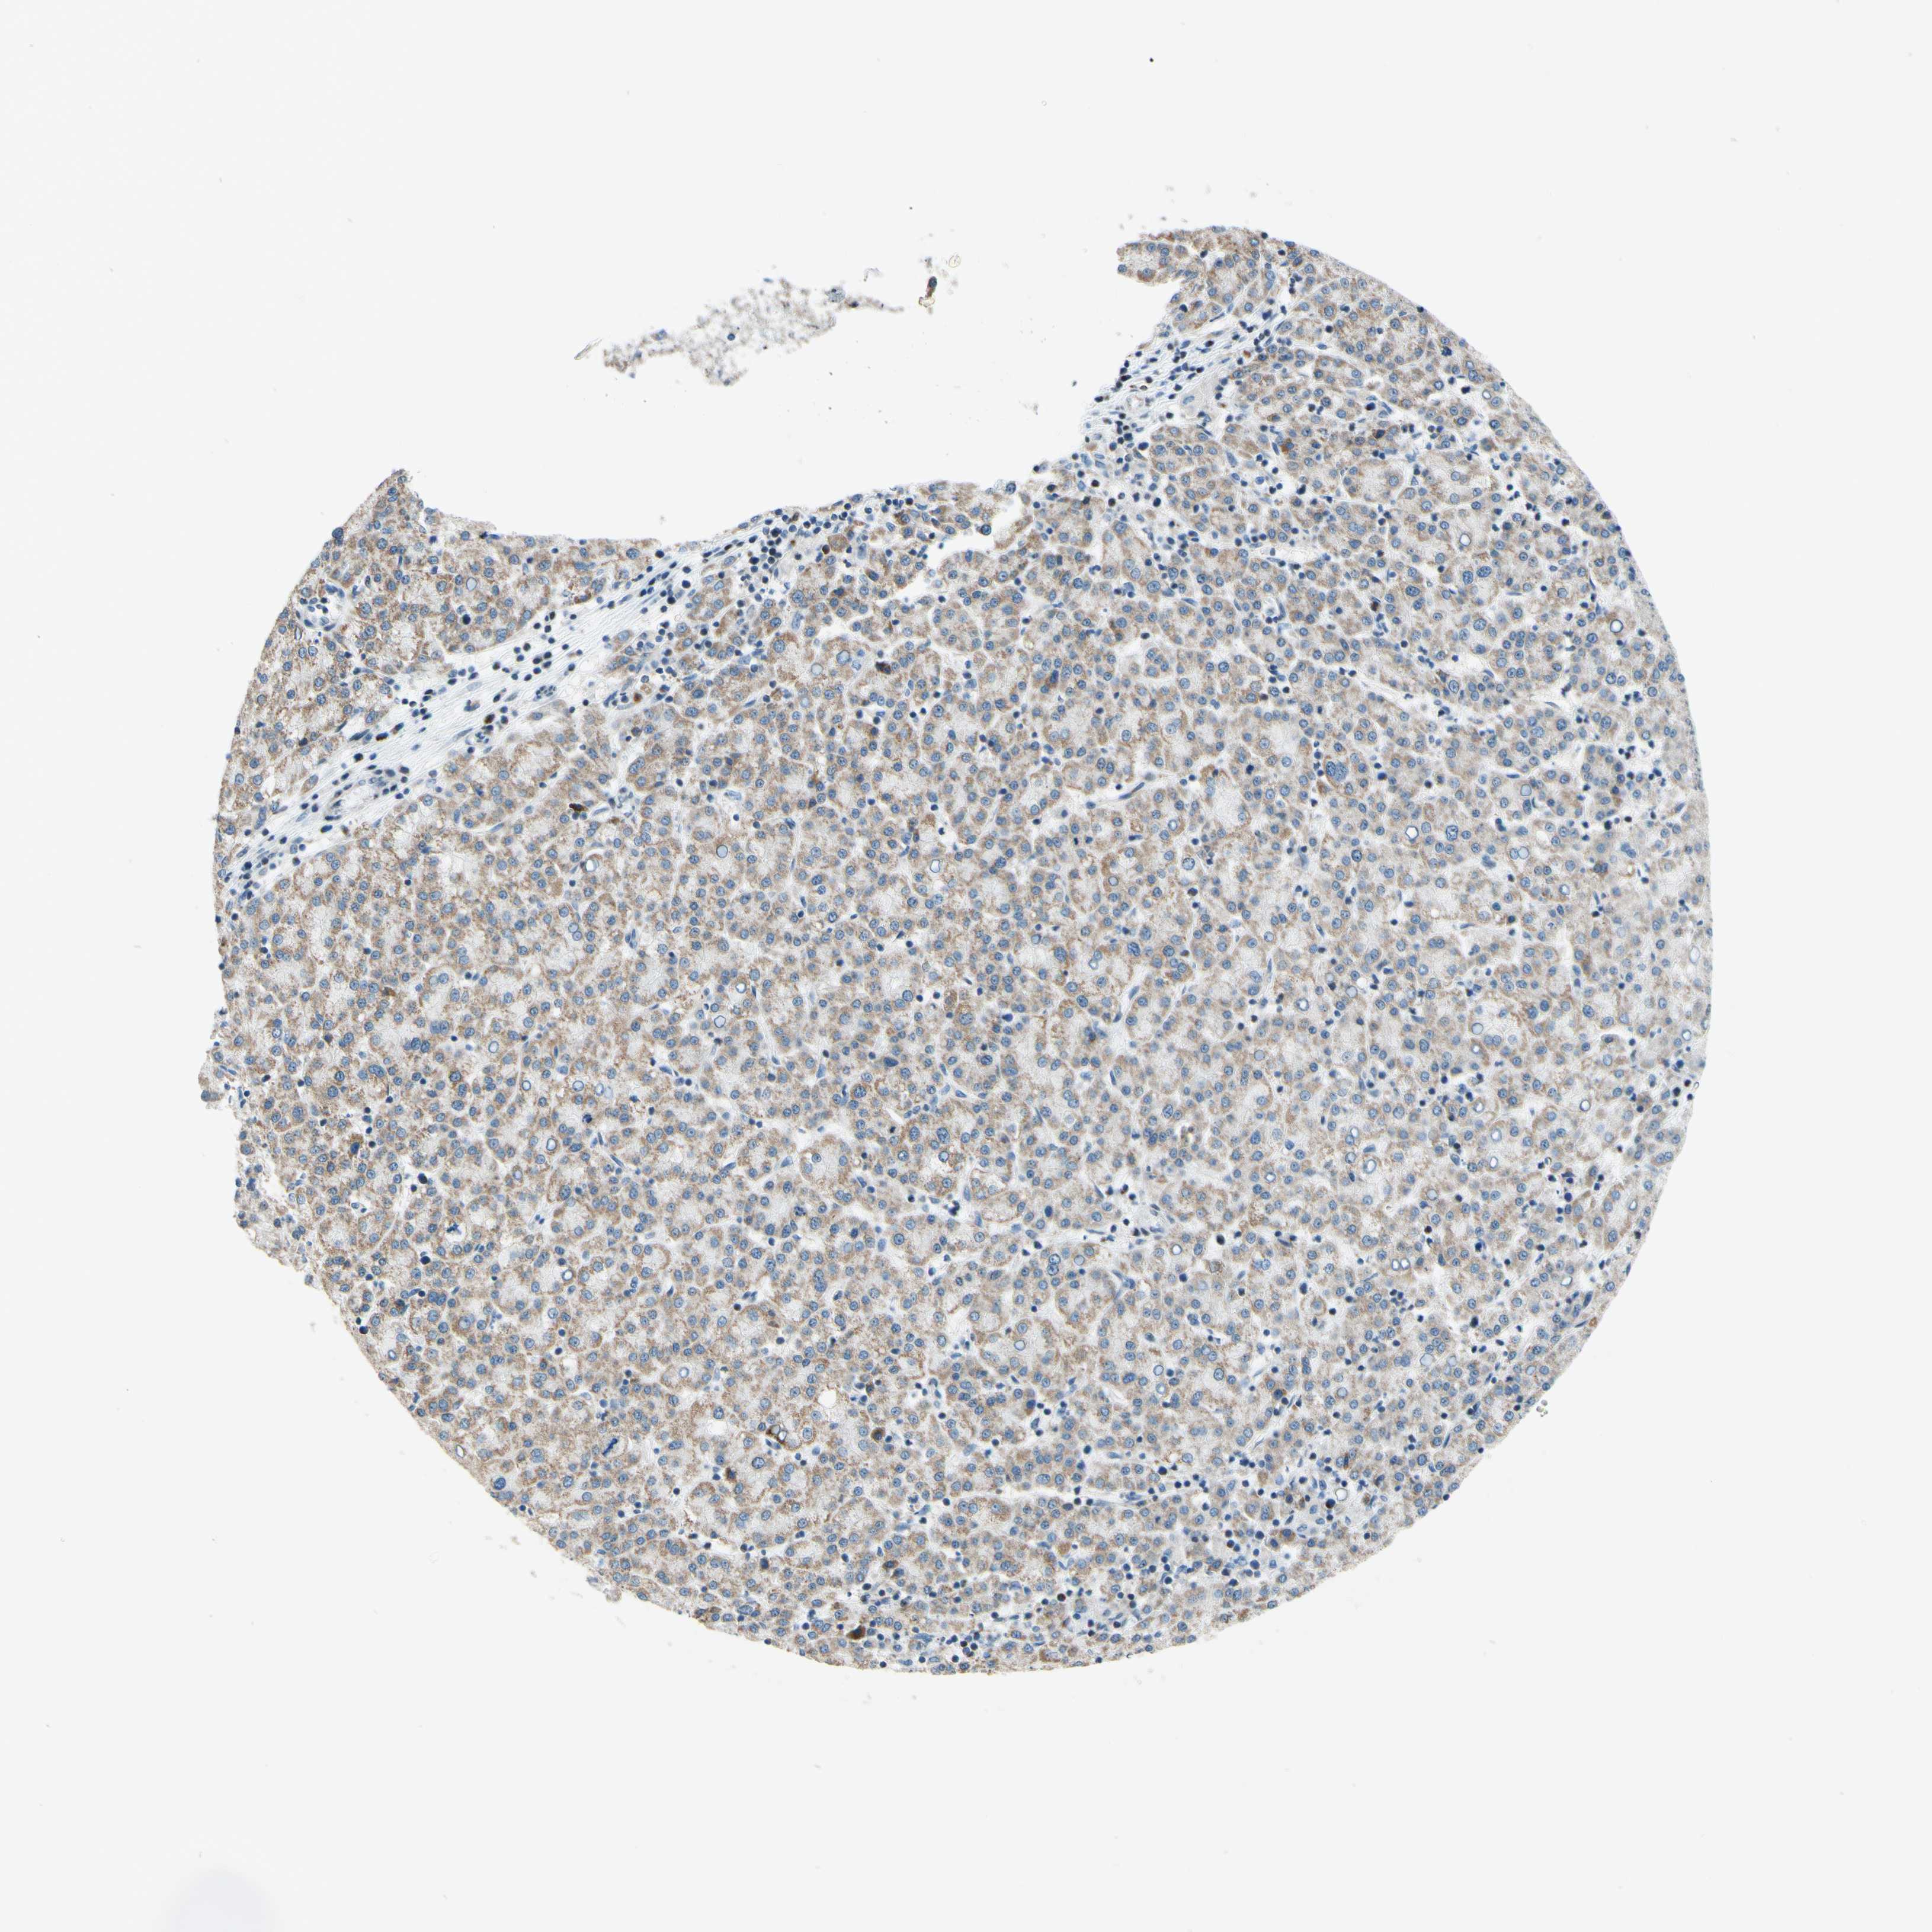

LIVER CANCER - Protein expressioni

A mouse-over function shows sample information and annotation data. Click on an image to view it in a full screen mode. Samples can be filtered based on level of antibody staining by selecting one or several of the following categories: high, medium, low and not detected. The assay and annotation is described here.

Note that samples used for immunohistochemistry by the Human Protein Atlas do not correspond to samples in the TCGA dataset.

Antibody stainingi

Antibody staining in the annotated cell types in the current human tissue is reported as not detected, low, medium, or high, based on conventional immunohistochemistry profiling in selected tissues. This score is based on the combination of the staining intensity and fraction of stained cells.

Each image is clickable and will lead to virtual microscopy that enables deeper exploration of all samples and also displays staining intensity scores, fraction scores and subcellular localization as well as patient and tissue information for each sample.

Antibody HPA048677

Antibody HPA056480

Antibody CAB011574

Staining

High

Medium

Low

Not detected

Intensity

Strong

Moderate

Weak

Negative

Quantity

>75%

75%-25%

<25%

None

Location

Nuclear

Cytoplasmic/membranous

Cytoplasmic/membranous,nuclear

Carcinoma, Hepatocellular, NOS